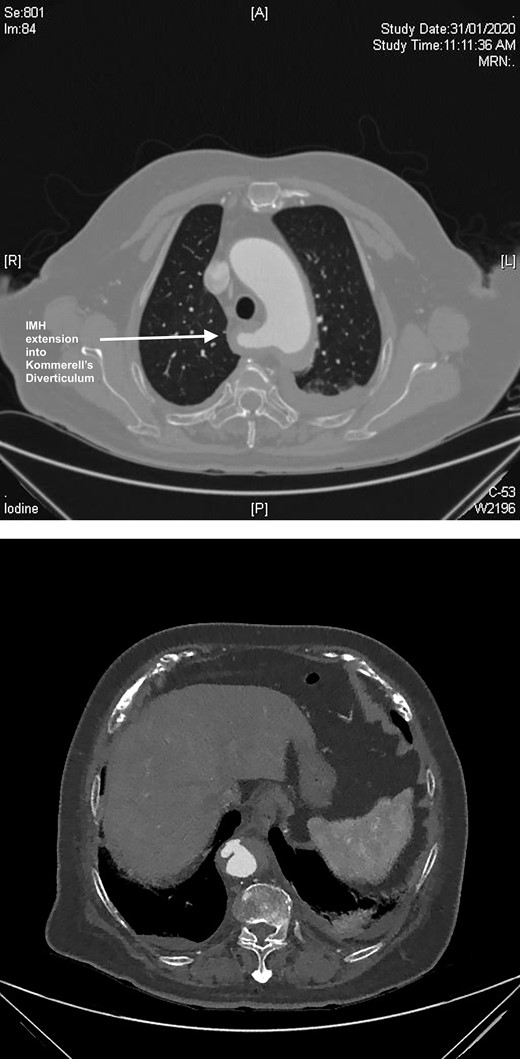

A 61-year-old male presented to a peripheral hospital emergency department with a 12-hour history of central chest pain with onset during sexual activity. He was an active smoker with poorly controlled essential hypertension. CT angiography showed an IMH from the left common carotid artery origin to the distal descending thoracic aorta, also involving the proximal ARSA and KD (Fig. 3).